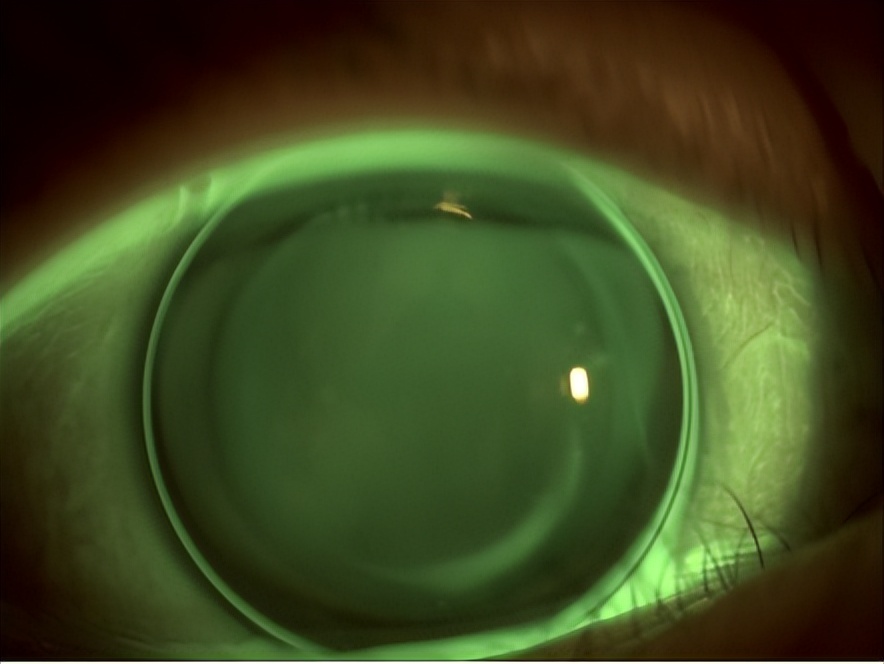

图4. 右眼原镜片荧光静态配适图(欧几里得 43.50/-4.50/11.0 AC42.75 T1.50)

镜片配适评估:右眼静态配适直径覆盖度好,呈中心定位,动态活动度佳,中央光学区镜片与角膜接触提示矢高偏低,水平方向定位区着陆理想,垂直方向定位区镜下泪液荧光逃逸。

综合评估:结合角膜地形图和镜片配适评估可知,右眼镜片的矢高不足,结合基线地形图资料可知矢高不足的原因为环曲量不足。右眼中央角膜上皮反复损伤也提示镜片与角膜顶点接触,造成机械性损伤的可能。应在不明显改动镜片其他参数的情况下,增加环曲量重新订片。